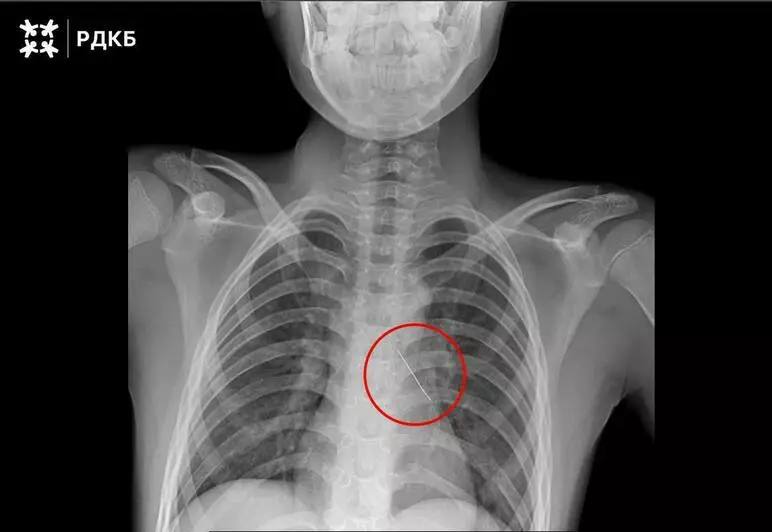

При поступлении мальчик мог говорить только шёпотом и жаловался на сильные боли в груди. Рентген показал, что булавка находится в области нижней доли левого бронха.

Булавку аккуратно извлекли под визуальным контролем с помощью оптических щипцов, это позволило минимизировать кровотечение. Контрольная рентгенография показала, что свободного воздуха в грудной полости нет.